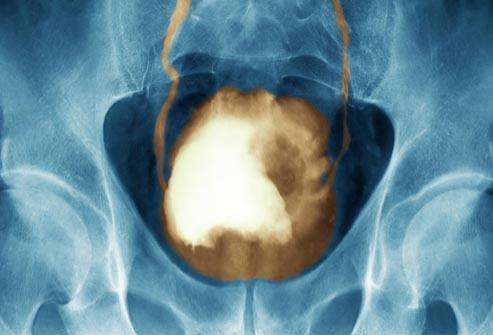

膀胱癌是常见的恶性肿瘤,指膀胱原发的癌肿。依其浸润深度的不同,可分为原位癌或浸润癌,膀胱癌在泌尿系统各癌肿中,发病率较高。以间隙性无痛性肉眼血尿为特点,可伴尿频、尿急、尿痛等类似膀胱刺激症状,晚期有严...【全文】

膀胱癌90%为移行细胞癌,鳞癌、腺癌占2%—3%。非尿路上皮膀胱肿瘤比较少见,多数为肉瘤。最常见的症状为无痛性肉眼血尿,发生率约85%。对疑似膀胱癌的患者要做什么检查确诊? 膀胱镜检查是诊断膀胱癌最重要而不可或...【全文】

膀胱肿瘤和性别关系密切,发病率在男性比女性高2-10倍。染料、皮革、橡胶、油漆、化学试剂、石油、美发师、铅厂工人等都是引发膀胱癌的危险因素。大多数的膀胱癌患者以无痛性肉眼血尿或显微镜下血尿为首发症状,对疑...【全文】